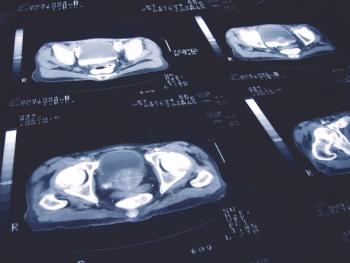

A recently FDA-approved drug offers patients with metastatic castration-resistant prostate cancer a newer treatment that improves survival, but is not curative of the disease, which means that more research is needed, according to an expert.

Patients with PSMA-positive metastatic castration-resistant prostate cancer can now be treated with Pluvicto, which may provide hope to an unmet need in this patient population.